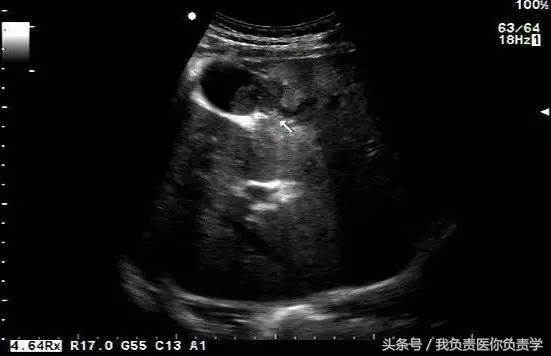

典型病例 1

患者男,64岁,因右上腹疼痛半月余就诊。查体发现右上腹部轻压痛,无发热。超声检查所见如下:

图1示胆囊增大,囊壁增厚,囊内透声差

图3示胆囊与囊性回声区间隐约可见裂隙相通

图4和5为局部放大图像,可见胆囊与囊性回声区间可见直径约2mm的通道

超声检查考虑为胆囊炎合并胆囊穿孔,后经CT检查证实。